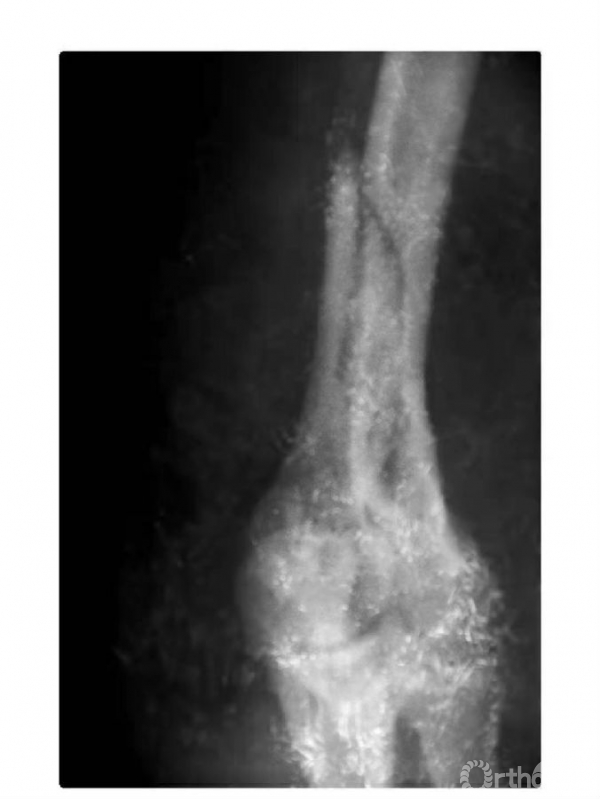

例3:肱骨内髁骨折,骨块向前上移位,并上尺桡关节分离致尺肱关节不稳,且桡骨干近段呈代偿性粗大(图6)。

图6